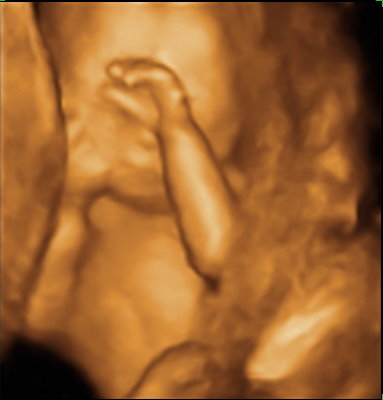

![IMG_0777[1] IMG_0777[1]](http://pic.pimg.tw/windy6710/1377096750-1641049764_n.jpg)

等了快一個月,今天要去醫院看羊膜穿刺報告結果了